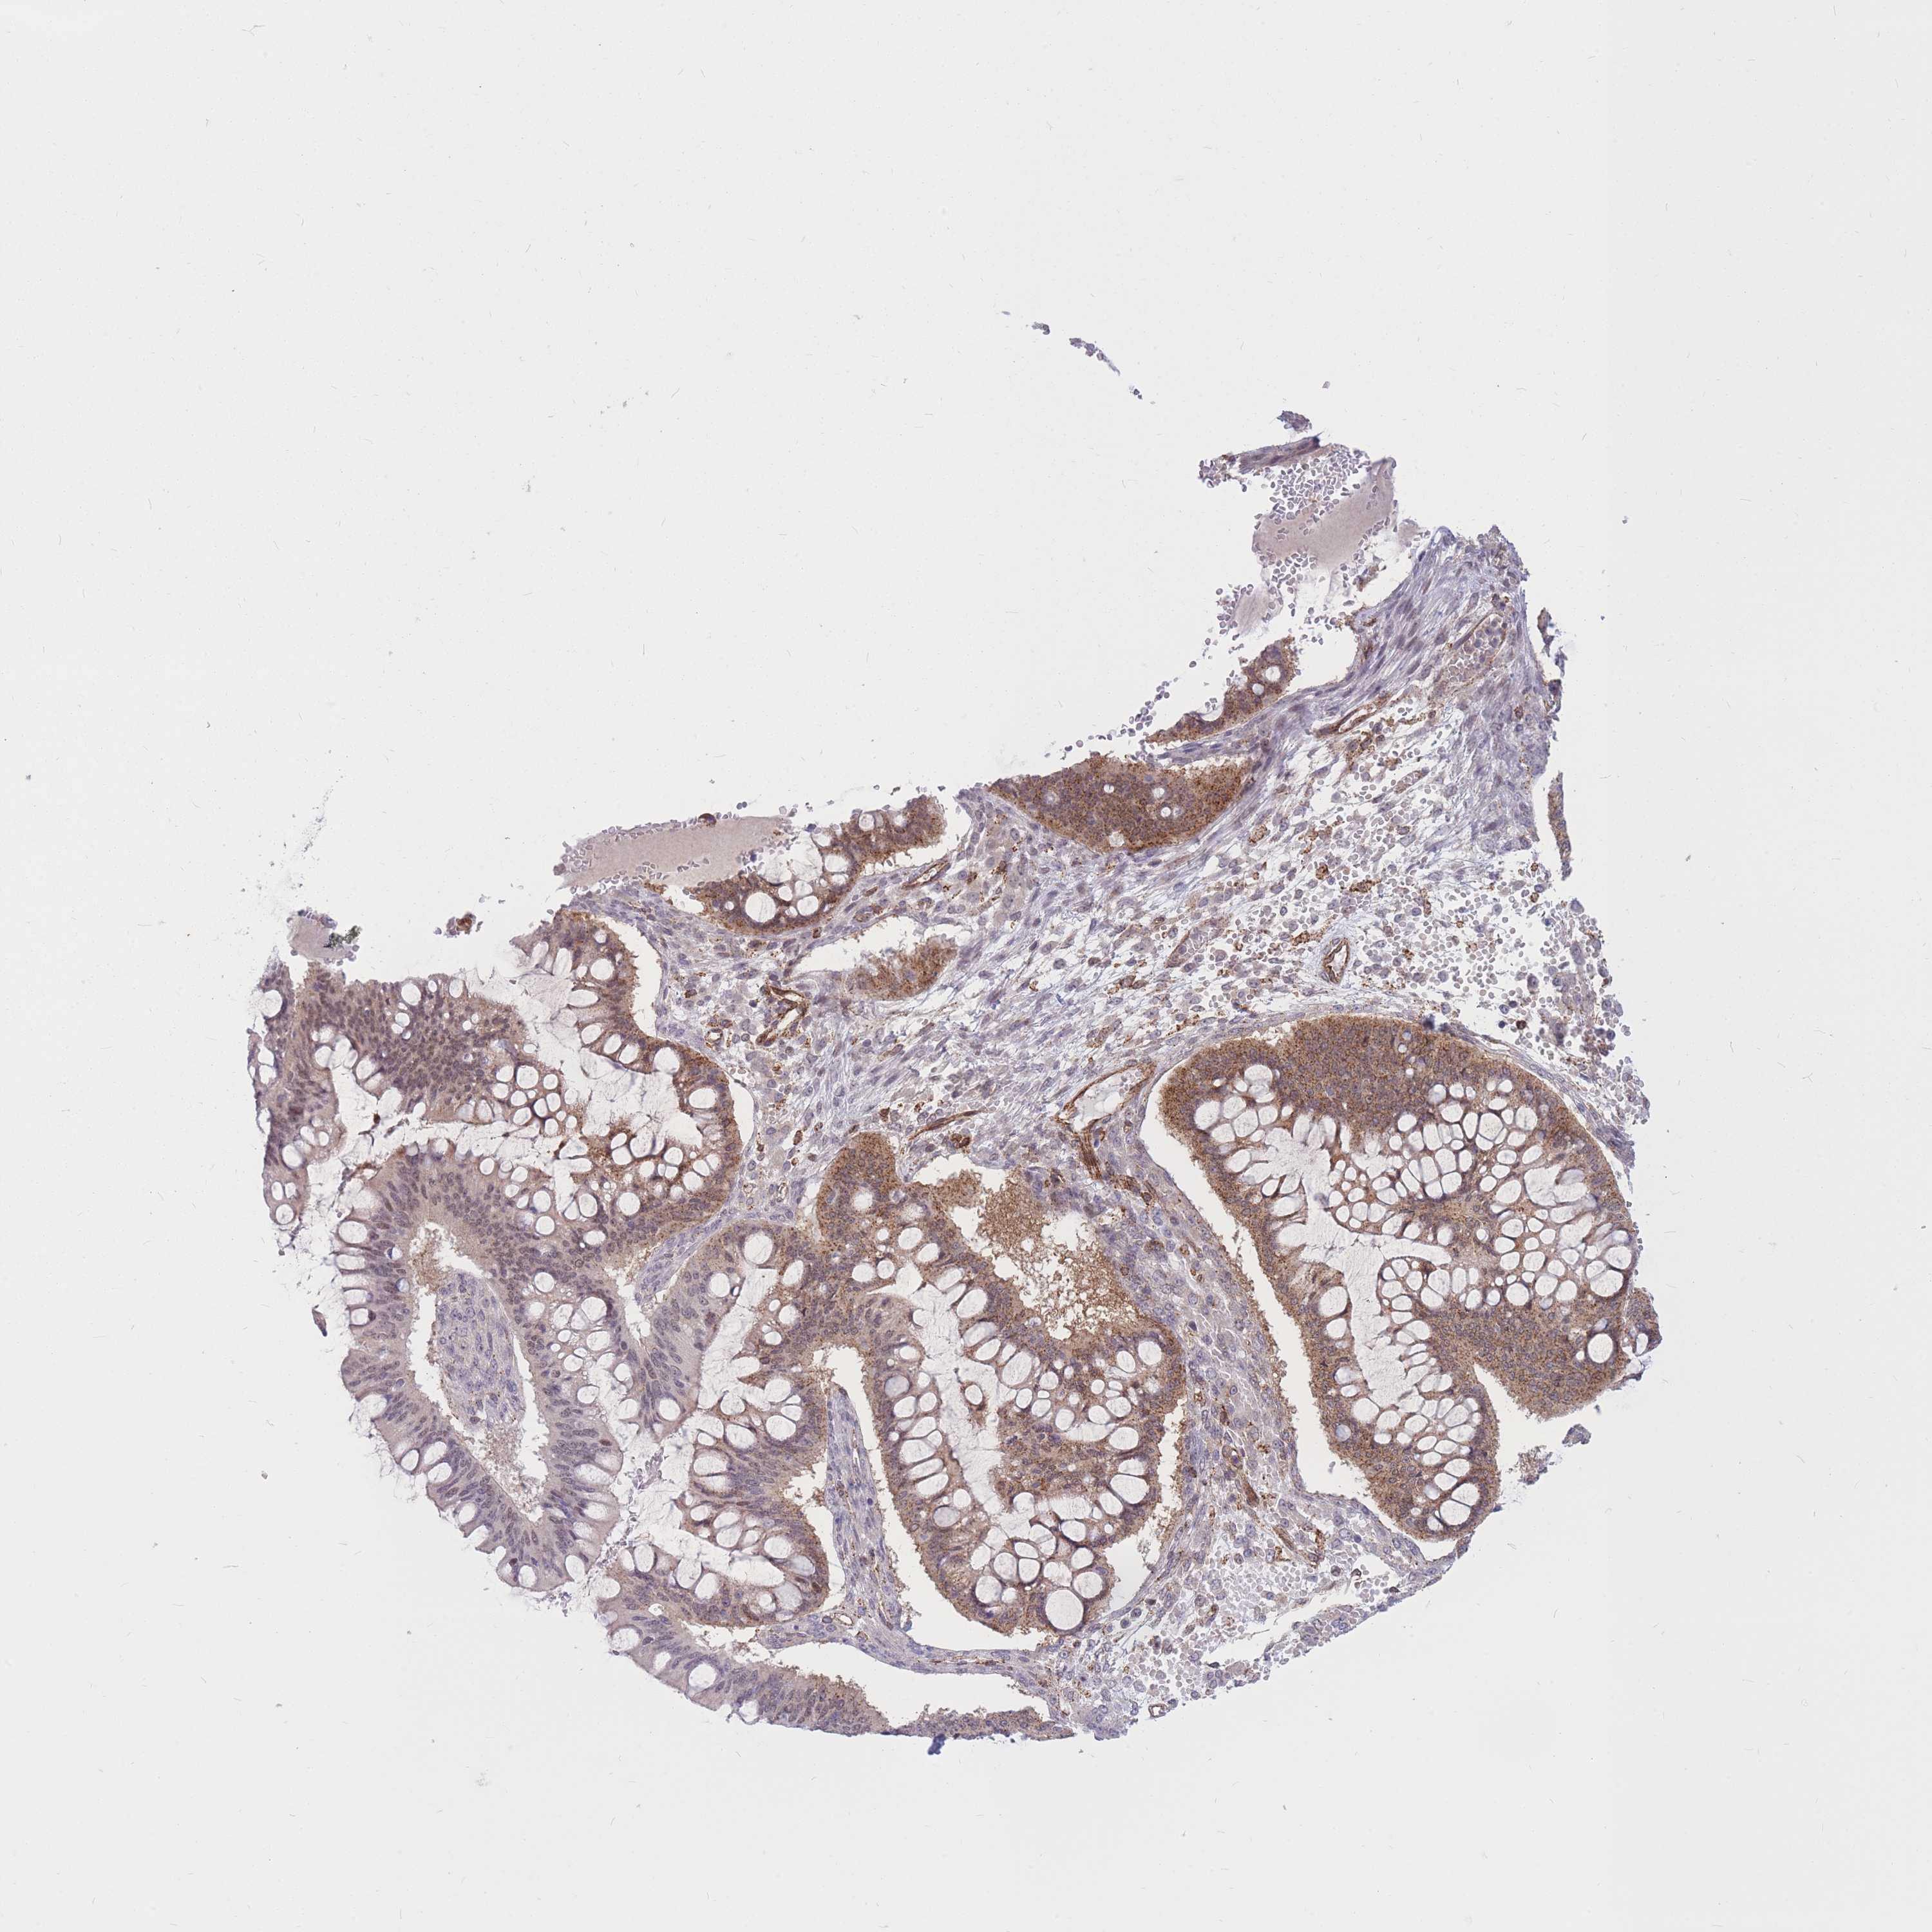

OVARIAN CANCER - Protein expressioni

A mouse-over function shows sample information and annotation data. Click on an image to view it in a full screen mode. Samples can be filtered based on level of antibody staining by selecting one or several of the following categories: high, medium, low and not detected. The assay and annotation is described here.

Note that samples used for immunohistochemistry by the Human Protein Atlas do not correspond to samples in the TCGA dataset.

Antibody stainingi

Antibody staining in the annotated cell types in the current human tissue is reported as not detected, low, medium, or high, based on conventional immunohistochemistry profiling in selected tissues. This score is based on the combination of the staining intensity and fraction of stained cells.

Each image is clickable and will lead to virtual microscopy that enables deeper exploration of all samples and also displays staining intensity scores, fraction scores and subcellular localization as well as patient and tissue information for each sample.

Antibody CAB017849

Carcinoma, endometroid

Cystadenocarcinoma, mucinous, NOS

Carcinoma, NOS